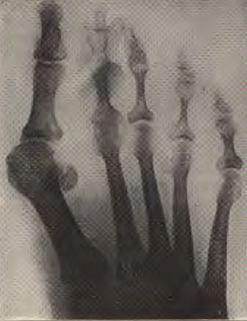

Attention Ladies! Here you see an x-ray of a foot in a sexy high heel. No words required.